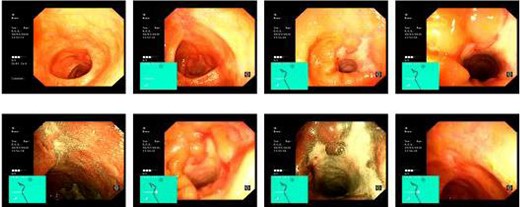

Computed tomography (CT) revealed a complex fistulous communication between the distal stomach and biliary tree with associated pneumobilia, and between the transverse colon and the distal stomach (Fig. 1). No gallstones were seen. Upper and lower gastrointestinal endoscopy was performed, revealing a prepyloric gastric ulceration and fistula (Fig. 2), with no obvious gastric pathology, which extended into the colon and a blind end structure assumed to be the gallbladder. Colonoscopy demonstrated an area of slight narrowing from the hepatic flexure to mid-transverse colon, with macroscopic colitis (Fig. 3). Biopsies were non-specific, with IBD a possibility, but the features were not pathognomonic.

Lower GI endoscopy demonstrating ulceration, stenosis and stricturing of the transverse colon.